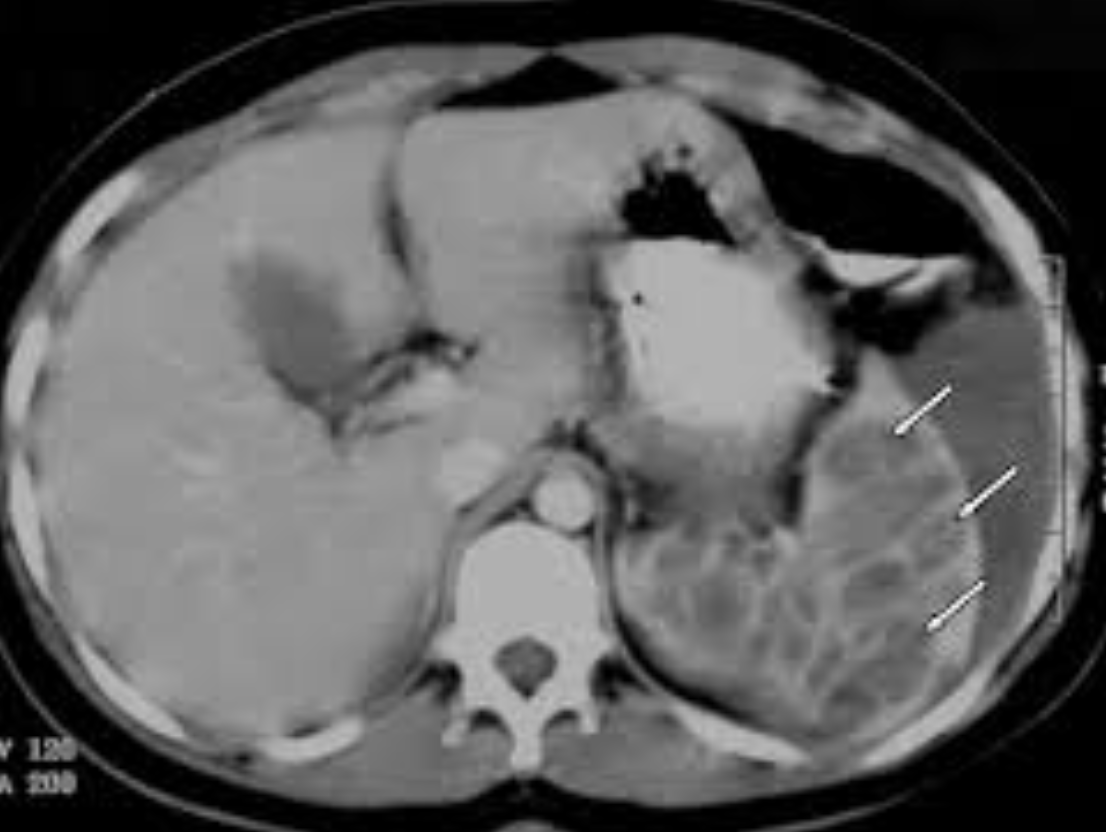

A soft tissue mass is noted in the fundus of the stomach, with lateral surface irregularity and gas locules on its surface. No exophytic/extra gastric component

No enlarged abdominal lymph nodes. No liver lesion within the limitation of the non contrast study.

Upper GI endoscopy revealed a lesser curvature mass. Pathologically proven GIST.

GISTs have a KIT receptor Tyrosine kinase